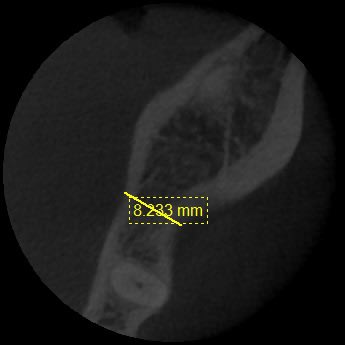

Lors de mon analyse scanner, je constate que au niveau de l'épaisseur crestale vestibulolinguale, je suis tout à fait a l'aise pr poser un 5x11,5mm.

En revanche, sur les 2 premiers millimétres de hauteur (au niveau cortical) , je n'ai pas 8mm en vestibulolinguale, comme il faudrait pr être bien pour poser un 5mm, mais j'ai tout juste 5mm (à peine)... La crête est en fait plus fine tout en haut de la crête, ce qui est je pense assez commun, puisque après l'extraction très ancienne, l'os s'est remodelé donnant cette petite lame de couteau (quand même épaisse d à peine 5 mm donc...)

Voici les photos

Épaisseur de crête au niveau du trait rouge.